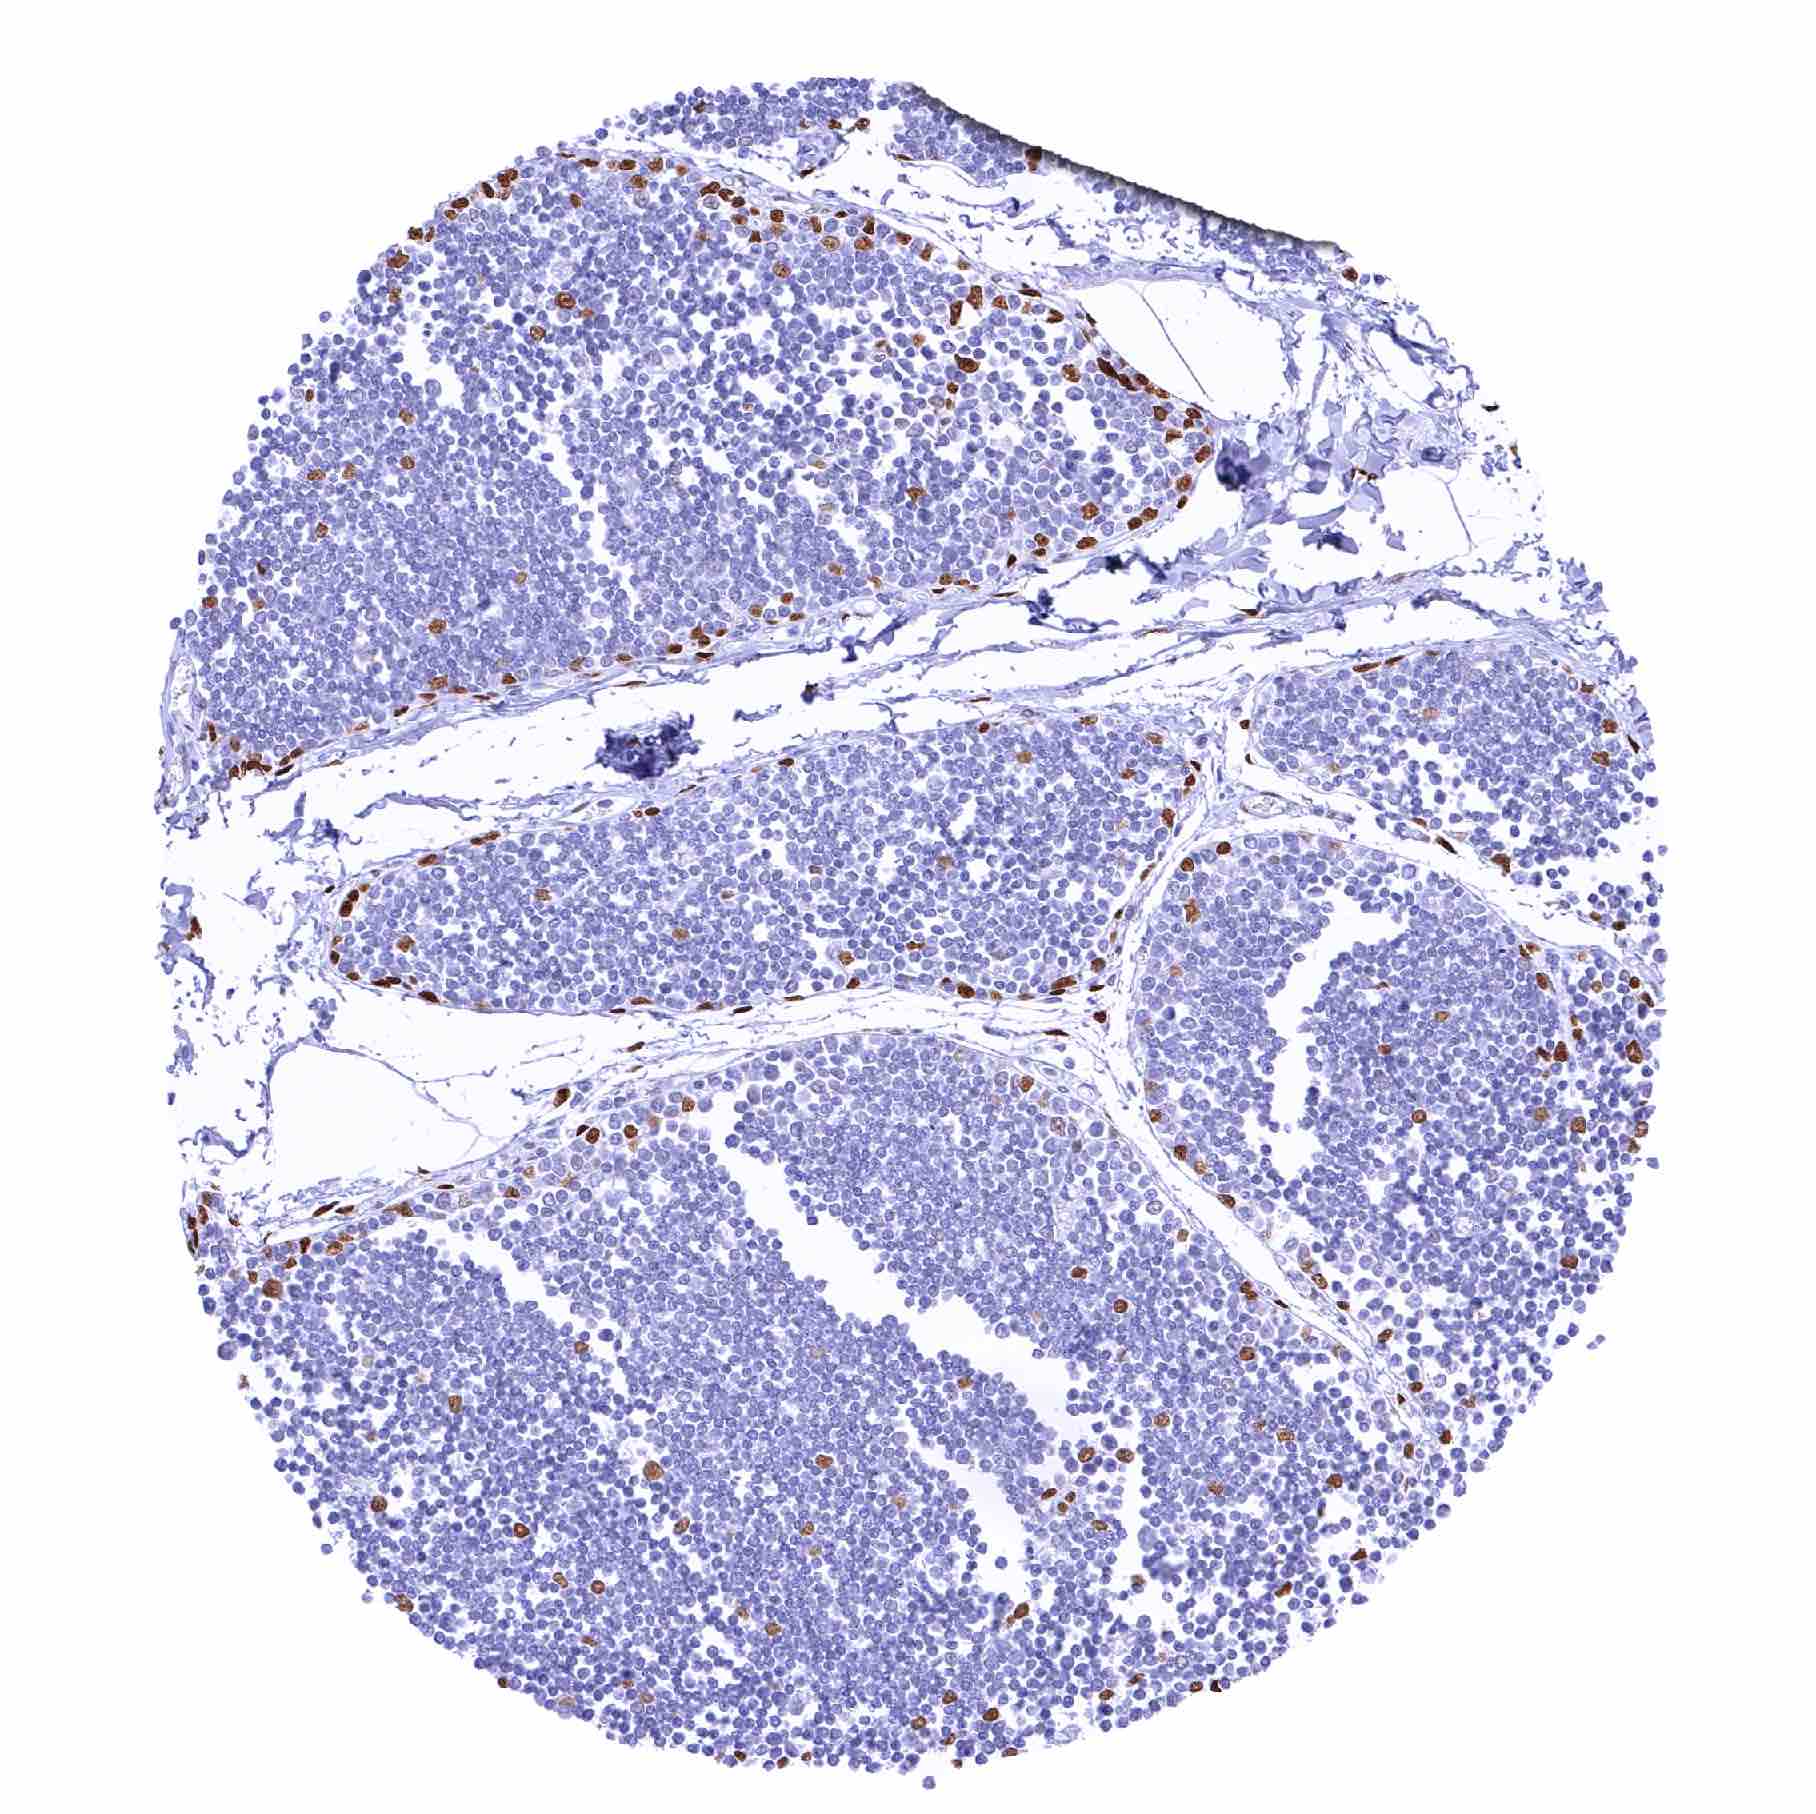

| Tonsil, surface epithelium – Significant decrease of nuclear NFIX staining of squamous epithelium from the basal-suprabasal to the superficial cell layers |